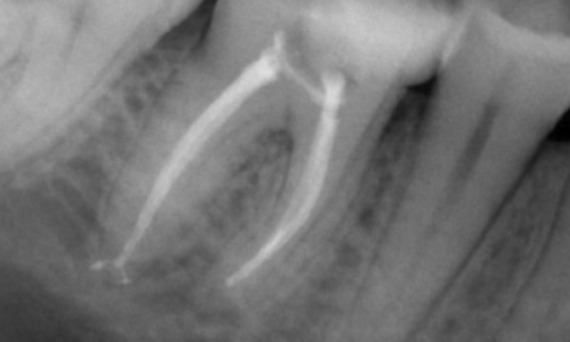

Avant : Présence d’une radioclarté périapicale principalement liée à la racine distale et perte de lamina dura sur la racine mésiale.

Après : La TruNatomie a été choisie dans ce cas pour permettre une approche avec levier de carie et pour se concentrer sur la préservation de la dentine péricervicale, en particulier sur l’aspect mésial où la dent avait une restauration plus minimale.